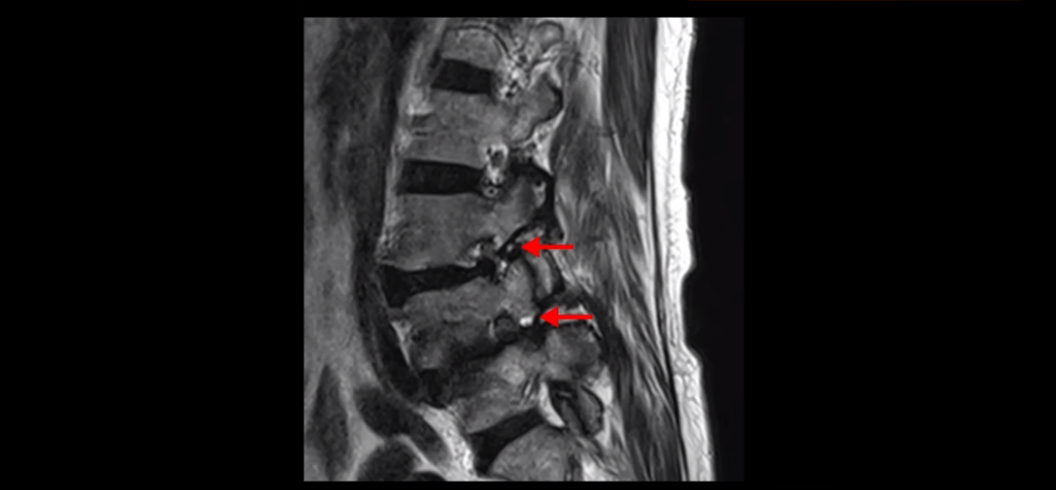

이분은 전방전위가 2단계로 매우 심하고,

신경 구멍도 두 마디나 좁아져있습니다.

전방전위와 협착이 다 심하니까 대학병원에서 나사 6개를 박는 유합술을 권유 받으셨는데요. 그런데 이분이 처음 아프게 된 건 작년 10월인데, 이분이 만약 아프기 전인 작년 초에 MRI를 찍었다면 지금의 MRI와 많이 다를까요? 아닙니다. 거의 차이가 없을 겁니다. 이미 척추 뼈는 많이 밀려나가 있고 신경 구멍은 똑같이 좁아진 상태였을 겁니다. 그 상태로도 전혀 안 아프게 아주 오랫동안 사신 겁니다. 그러다가 작년 10월에 무리한 일과 운동 때문에 허리 근육에 문제가 생기면서 신경이 눌리기 시작한 겁니다. 만일 아프지 않을 때 MRI를 찍고 척추 뼈가 밀려나가고 신경이 눌렸으니까 나사 박는 수술을 하자고 하면, 수술을 받을 사람이 있을까요?